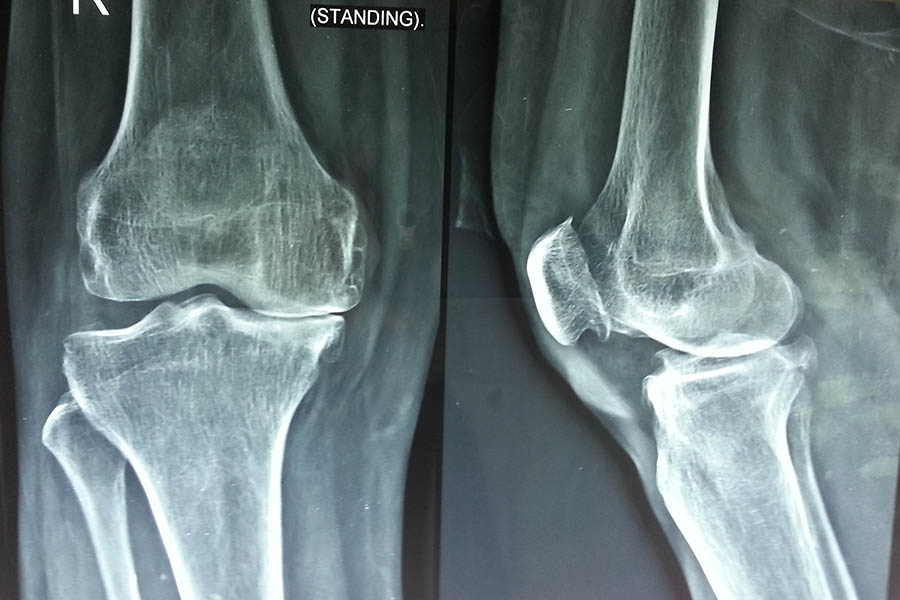

Total Knee Replacement

Case 2